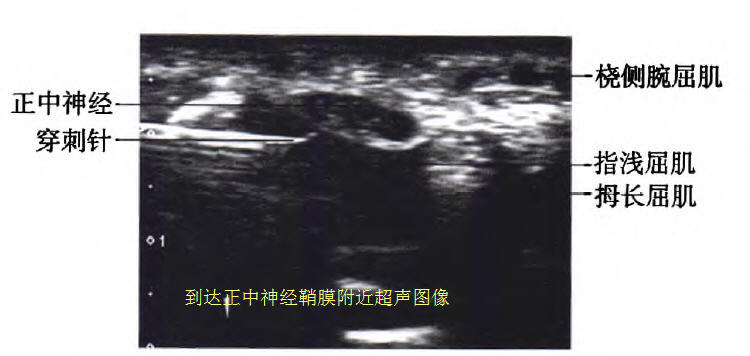

然后采用平面内技术,在超声的引导下从尺侧人路,针尖从指浅屈肌与指深屈肌之间穿行到达正中神经的神经鞘膜附近。

注人少许药液,剥离正中神经与周围组织的粘连,回抽无血后缓慢注入3 ml含有布比卡因4.5 mg、曲安奈德5 mg注射液,注射完后嘱咐患者休息30 min。